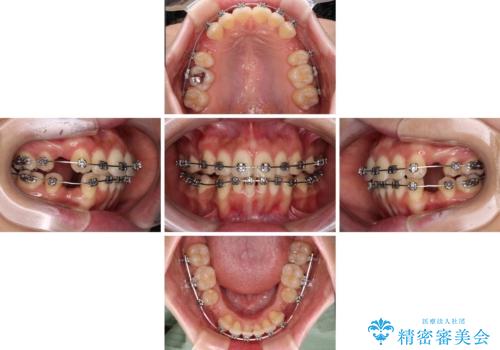

- メタルブラケット

- 2年2ヶ月

- 10-30回

上下ともに歯列が前方に突出していたため、上下左右の第一小臼歯4本を抜去し、ワイヤー装置による矯正治療を行うこととしました。

舌の突出癖による影響もあったため、舌のトレーニングを並行して実施しました。

舌の突出癖がなかなか改善されず、上下前歯の接触がやや甘い状態での仕上がりとなりました。

接触が甘い場合、上顎前歯の叢生が後戻りを起こしやすくなるため、治療終了後の保定期間でも舌のトレーニングを継続するように指示しています。